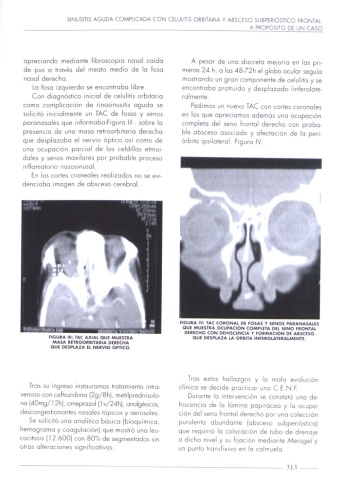

FIGURA IV: TAC CORONAL DE FOSAS Y SENOS PARANASALES

0U! MUESYRA OCUPACION COMPLETA Dil SENO FRONTAL

DERECHO CON DEHISCENCIA Y FORMACION DE ABSCESO

FIGURA III: IAC AXIAL QUE MUESYRA QUE DESPLAZA LA ORBIYA INFEROLAYERALMENTE.

MASA RETROORBIYARIA DERECHA

QUE DESPLAZA EL NERVIO OPYICO.

como complvcooón de rmosmusms agudo se Pedimos w nuevo TAC con corms coronoles

sollcnó nmoolmenre un TAC de fosos y senos en los que apreciamos odemos uno ocupocmjn

poronosolcs que IHFOHhObO'FIgUKO III sobre Io complete d0! seno "rorª'ol derecho con probe

presenca de una moso re'roorbntaua derecho

ble obsceso asoclodc y ofccfooon de lo perl-

que desplozobo el ncrwo óphco así como de mbno prIloteroi ngwg IV